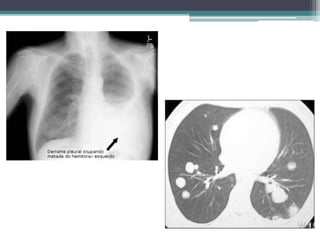

Avaliação diagnóstica

• Exames de imageamento

▫ Radiografia de tórax;

▫ Tomografia computadorizada;

▫ Imageamento por ressonância magnética;